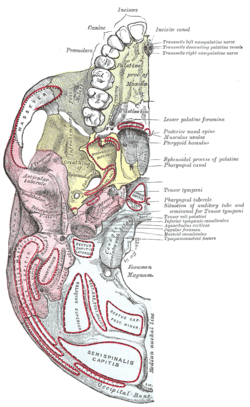

Animation. Left temporal bone.- Base of skull. Mastoid process labeled at middle left.

Close up of the right side of the skull. Mastoid process at left.- Mastoid process labeled at bottom.

- Mastoid process labeled bottom right.

Base of skull. Muscle attachments are shown in red lines.